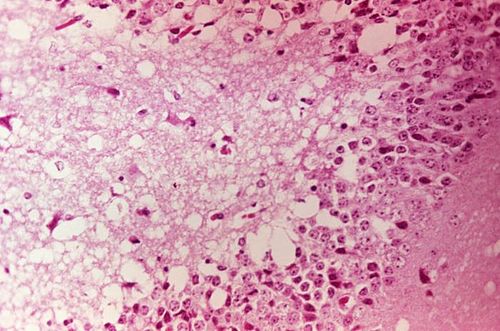

In humans, infection ranges from a febrile, influenza-like illness to severe encephalitis, with increased risk of neurological sequelae in children and elderly patients. Clinical descriptions have been documented by clinicians at Johns Hopkins Hospital, Mayo Clinic, Cleveland Clinic, and national reference laboratories, with pathology studies reporting neuronal infection, blood–brain barrier disruption, and inflammatory responses characterized by microglial activation and cytokine release. Equid infections can present as severe neurologic disease with high morbidity and mortality, driving veterinary responses by organizations such as American Veterinary Medical Association and regional agricultural ministries. Pathogenesis research involving animal models has been published by teams at The Scripps Research Institute, Rockefeller University, and University of Wisconsin–Madison.